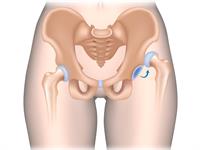

Izmežģījums ir pilnīga kaulu locītavu galu pārvietošanās attiecībā vienai pret otru. Aktīvas kustības kļūst neiespējamas.

Gūžas locītavas izmežģījums